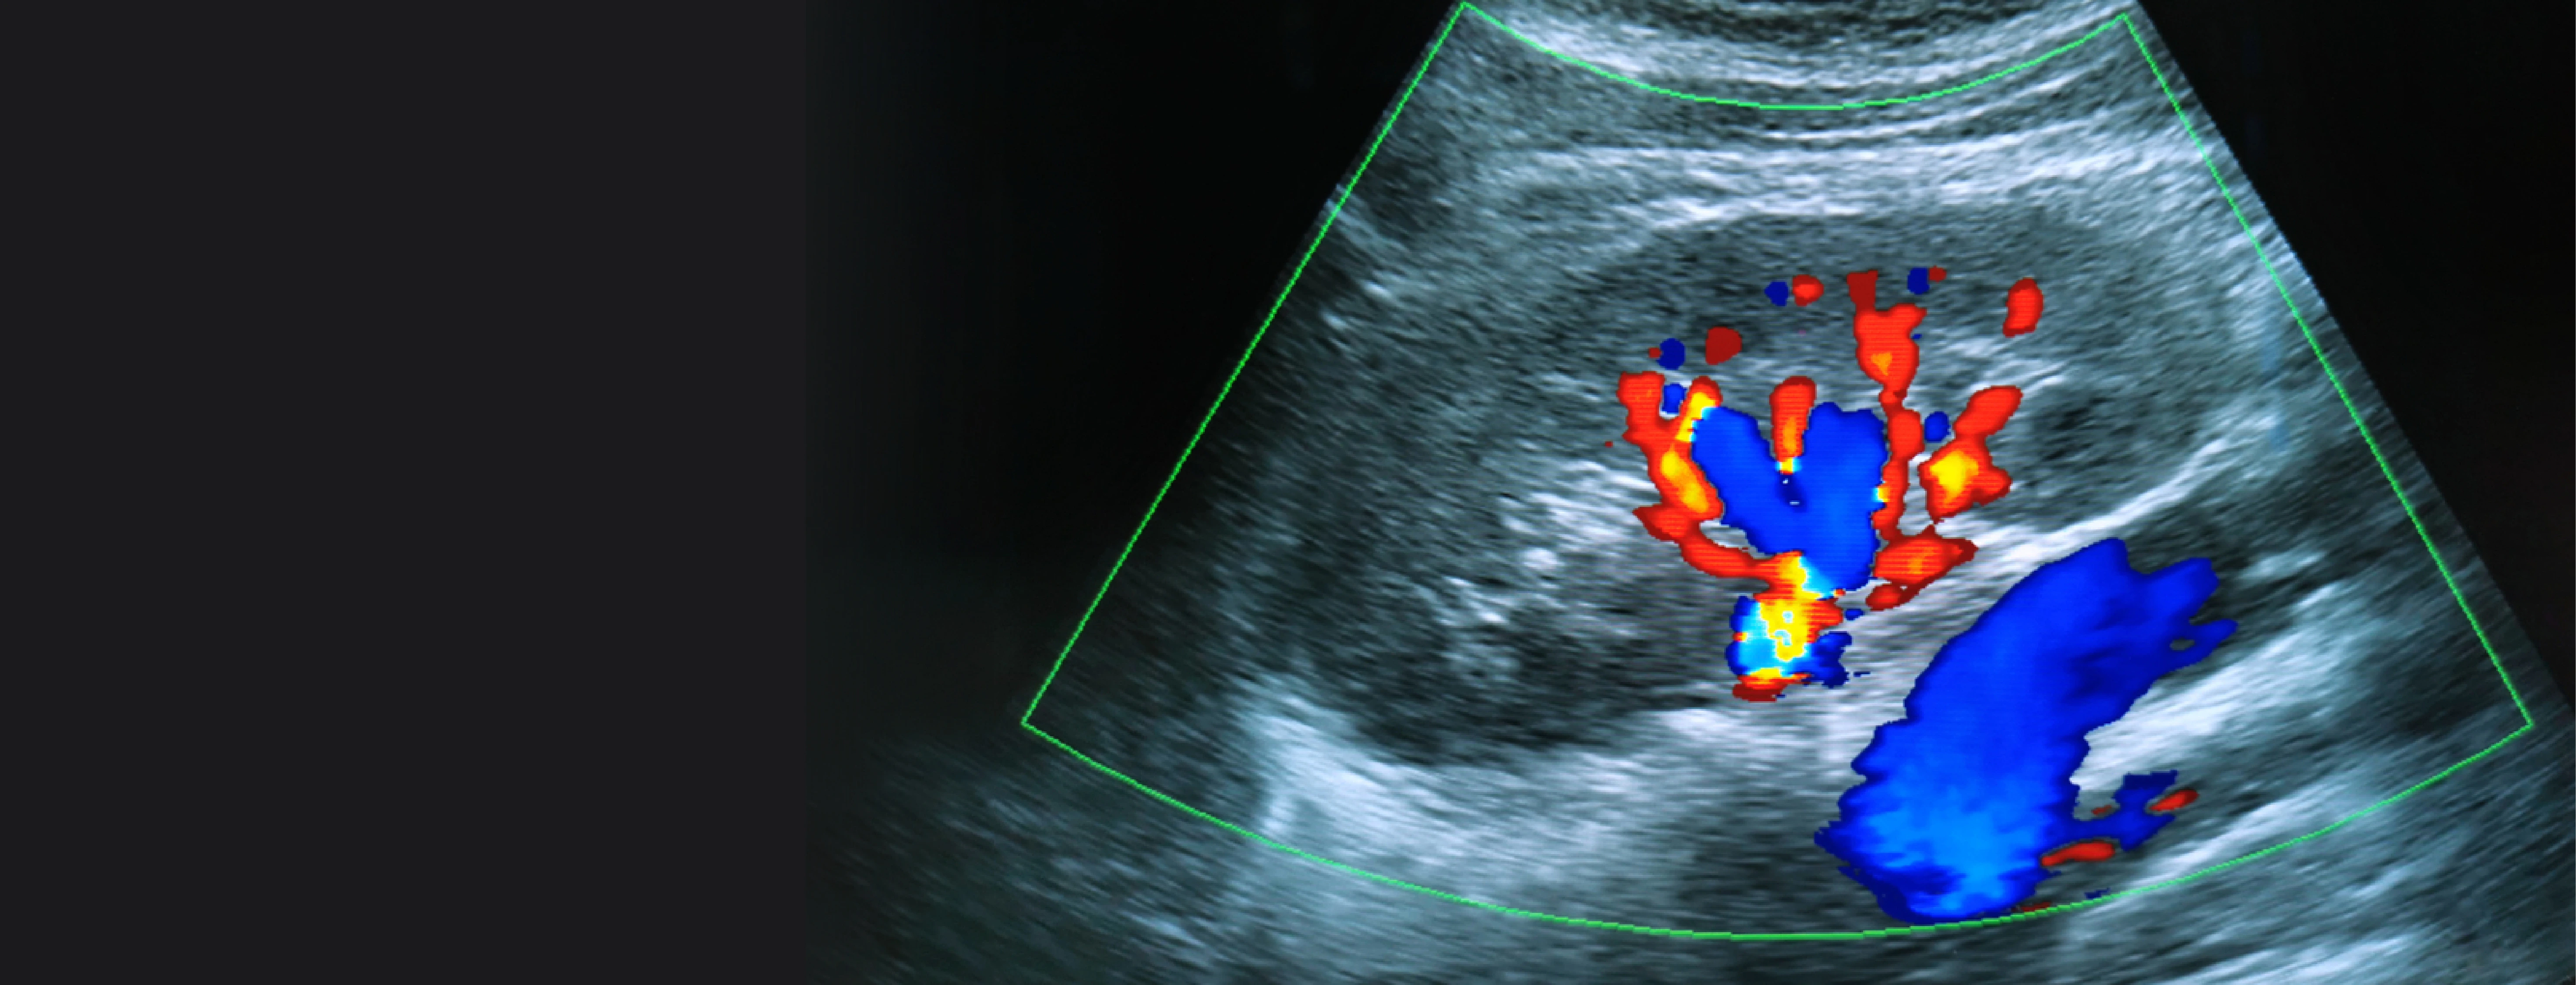

A: Color doppler shows blood flow in color; duplex doppler provides flow data and structural images for more detailed assessment.